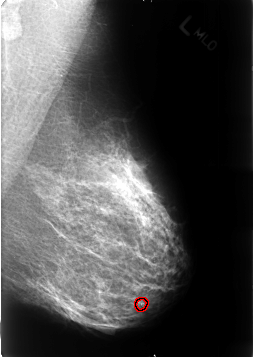

B_3245_1.LEFT_MLO

FILE: B_3245_1.LEFT_MLO.OVERLAY

TOTAL_ABNORMALITIES 1

ABNORMALITY 1

LESION_TYPE CALCIFICATION TYPE LUCENT_CENTER DISTRIBUTION N/A

ASSESSMENT 2

SUBTLETY 5

PATHOLOGY BENIGN_WITHOUT_CALLBACK